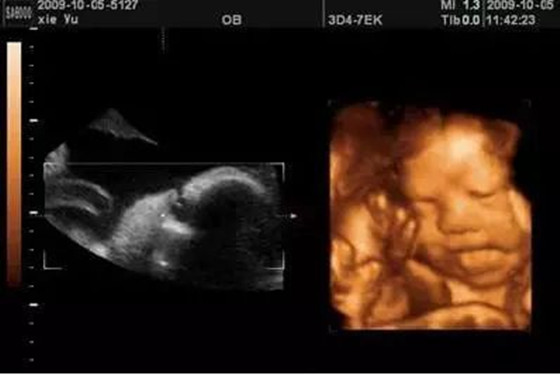

胎儿五个月彩超图 怀孕五个月胎儿真实图片

怀孕五个月时胎儿已经长出了头发,眉毛和指甲了,此时胎儿的头部如鸡蛋般大小,他们身上的皮肤也显得不那么透明了,胎儿宝宝在麻麻肚子里可以自由的活动,一些比较调皮的胎儿会毫不留情的在麻麻肚子里“闹腾”,从四维彩超图片可以观察出胎儿的具体动态,他们偶尔会吸吮自己的手指玩耍,好似困了还会打打哈欠,饿了也会做出吞咽动作,有的时候会对麻麻的肚皮“拳打脚踢”,有时也会揉揉自己的眼睛,还有的时候胎儿也会玩弄脐带等等,总之胎儿宝宝在麻麻肚子里面不会那么“乖巧听话”,他们也有自己的一套作息时间,饿了会吃,泛了会睡,无聊时也会玩耍戏弄。